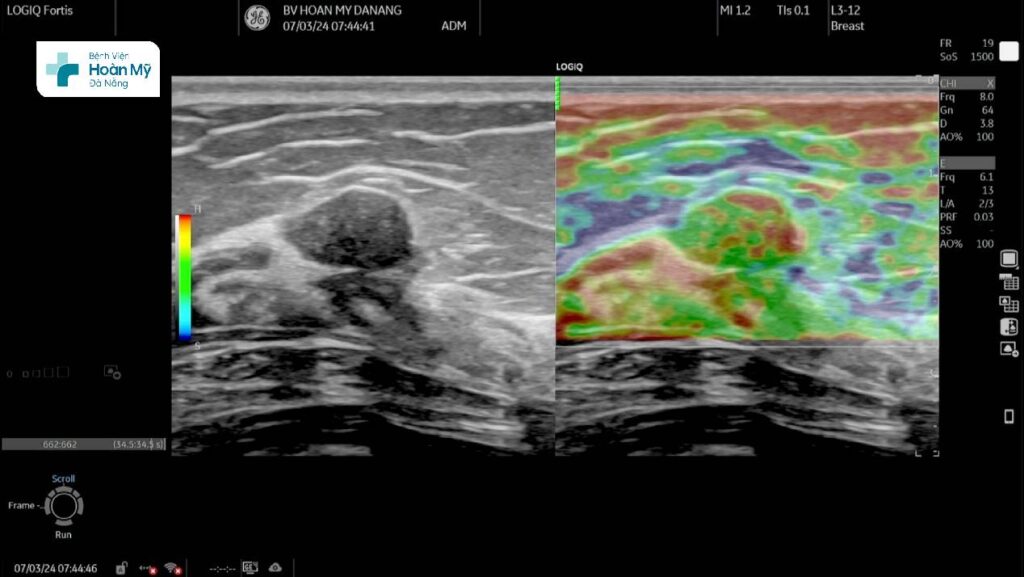

Siêu âm chẩn đoán tổn thương u vú trên máy siêu âm cao cấp LOGIQ Fortis thế hệ mới

Một ví dụ khác khi ứng dụng siêu âm đàn hồi mô như sau: Bệnh nhân nữ trung niên, đi khám tầm soát, phát hiện khối u vú trái. Trên siêu âm thường quy thấy tính chất khối hình bầu dục, giảm âm nhẹ, bờ tương đối đều, giới hạn rõ, trục song song, tưới máu ít xếp nhóm BIRADS 3. Khi làm siêu âm đàn hồi bán định lượng (strain elastography) có hình ảnh phù hợp Tsukuba elasticity score 2 cũng cố thêm khả năng lành tính cao của tổn thương, nhờ đó người bệnh yên tâm theo dõi mà không cần sinh thiết.